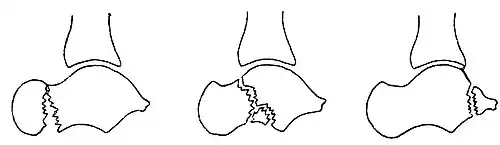

Osul trigon (Os trigonum) (din latina trigonon = triunghi) este un osișor supranumerar (accesoriu) independent al tarsului situat în partea posterioară a talusului, lângă tuberculul lateral al procesului posterior al talusului. Incidența sa a fost estimată în literatura de specialitate a fi între 1,7 și 8% în populație, iar în 1,4% este bilateral. La examenul radiologic, prezența sa trebuie să se distingă clar de fractură Shepherd (fractura tuberculului lateral) care întrerupe baza procesului posterior al talusului. Tendonul mușchiului flexorul lung al halucelui trece medial de osul trigon.[1][8][9][38][52][53][54][55][56][57][58]

După cum sugerează și numele, osul trigon are de obicei o formă triunghiulară, cu 3 fețe (anterioară, inferioară și posterioară), dar poate avea și o formă rotunjită sau ovală. Osul trigon este compus dintr-o parte corticală periferică și un centru spongios. De obicei, osul trigon are trei fețe: una anterioară, alta inferioară și a treia posterioară. Fața anterioară articulară are de obicei o formă de semilună și formează cu tuberculul lateral al talusului o articulație de tip sincondroză sau este legat de acesta printr-un țesut fibros, fibrocartilaginos sau cartilaginos. Fața inferioară, calcaneană, este și ea articulară, și poate să se articulează cu fața superioară a calcaneului, participând la coaliția (sinostoza) talocalcaneană. Fața posterioară este nearticulară. Osul trigon este cel mai adesea unic și măsoară mai puțin de 1 cm pe axul mare. El poate fi, de asemenea, bipartit (divizat în două părți) sau multipartit (divizat în mai multe părți). Osul trigon fuzionat cu tuberculul lateral este numit proces trigonal[14][52][53][59]

Osul trigon provine dintr-un centru de osificare cartilaginas secundar, care se formează în partea posterioară a talusului, între 11 și 13 ani la băieți și între 8 și 10 ani la fete. În mod normal, acest nucleu de osificare fuzionează cu tuberculul lateral al talusului în cursul primului an de la apariția sa, participând la formarea procesul posterior al talusului. Atunci când această fuziune antrenează formarea unui proces talar posterior mare și intact, acesta este numit procesul talar posterior hipertrofic sau "procesul Stieda." În absența fuziunii centrului de osificare cu tuberculul lateral al talusului, din acest centru de osificare se formează un os independent, numit osul trigon.[52][53]